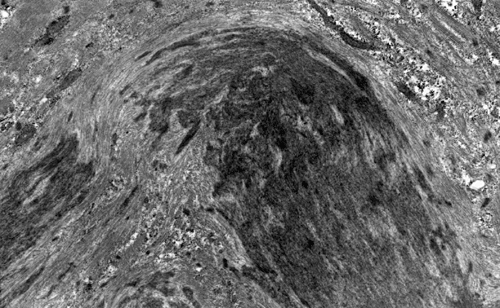

On hematoxylin-eosin stained sections, there is an increased variation of fiber diameter with many atrophic fibers intermingled with fibers of normal caliber. There is no evidence of fiber grouping or perifascicular atrophy. No inflammatory cells are present. There is also mild interstitial fibrosis (Panel A). On higher magnification, many fibers have a round concentric structure (Panel B). Irregular, centrally located depositions are also identified on modified Gomori's trichrome. The concentric nature, however, is not as obvious as in the hematoxin-eosin stained sections (Panel C). Type I and II fibers are not clearly separated in the ATPase preparation at pH 9.4. This is a common situation in chronically ill muscle (Panel D). The type I fibers are unusually dark. There is an increase in the proportion of type I fibers. The atrophic fibers are usually type II fibers. The concentric lesions are found predominantly in type I fibers (Panel E). There is an increase in PAS staining which is consistent with increased glycogen storage (Panel F). No increase in lipid content is demonstrated by oil red O (Panel G). On NADH-TR reaction, the concentric structures appear to have a clear central core that is devoid of enzymatic activity, a rim with intense enzymatic activity and a surround zone with relatively normal reactivity. These features are classic for target fibers (Panel H and I). No deficiency of laminin-2 (merosin) (Panel J) or dystrophin (Panel K) is demonstrated by immunohistochemistry. The central lesions are also immunoreactive for both laminin-2 and dystrophin. Immunohistochemistry for desmin demonstrate a core of strong immunoreactivity and also strong reaction in the sarcoplasmic membrane (Panel L and M). The target structures are also well demonstrated on semithin sections (Panel N). On electron microscopy, z-disc streaming is a common finding and they are often admixed with a substantial amount of dense granular electron dense substance (Panel O and P). There are also numerous cytoplasmic bodies characterized by radiating intermediate filaments (spheroid bodies) (Panel Q and R).